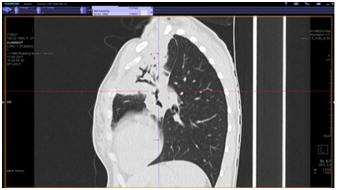

КТ органов грудной клетки (от 17.08.2017 г.)

Заключение: массивные инфильтративные изменения в верхней доле левого легкого полностью неясного генеза, возможно имеет место как воспалительный специфический характер поражения с распадом, так и осложнение пневмонии с формированием абсцесса, злокачественный процесс с распадом мало вероятен.